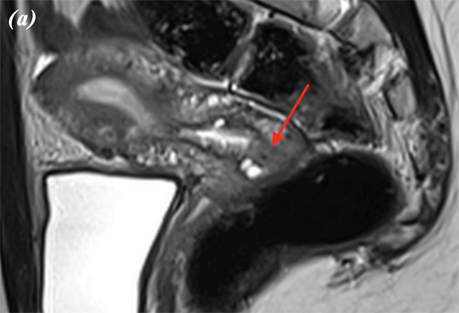

При виконанні магнітно-резонансної томографії (МРТ) органів черевної порожнини та малого таза від 15.03.2023 р. виявлено, що заочеревинні лімфатичні вузли не збільшені. Тіло матки розміром 45×46×47 мм. Зональна структура збережена, відповідно віку. Зовнішній контур тіла матки чіткий та рівний. Шийка матки — структурна, розміром 25×20×30 мм. Цервікальний канал рівний та чіткий. У проєкції входу в шийку матки по правій стінці на 5 год умовного циферблату виявлено екзофітний інфільтрат розміром 12×12 мм. Параметральна клітковина не змінена.

Вагіна візуально не змінена. Яєчники в яєчникових ямках, структурні, не збільшені, візуально не змінені. Правий яєчник розміром 30×12×35 мм, лівий яєчник розміром 18×20×20 мм. У товщі лівого яєчника тонкостінна функціональна кіста 16 мм у діаметрі. У Дугласовому просторі сліди вільної рідини (рис. 4).

Рис. 4. МРТ органів черевної порожнини пацієнтки. МРТ-ознаки РШМ, без поширення на суміжні органи: a — сагітальна проєкція; b — фронтальна проєкція